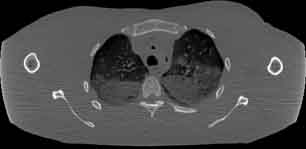

Visible Human male: Sectio transversalis 1354

CT

NMR

Pd T1 T2